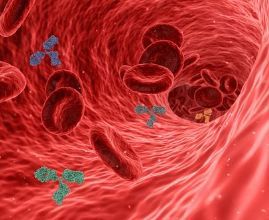

혈액 속 지방 수치가 높다는 말, 한 번쯤 들어보셨죠?

바로 **고지혈증(고콜레스테롤혈증)**입니다.

고지혈증 증상 2. 혈액검사에서 LDL 콜레스테롤 수치 상승

눈에 보이지 않지만 가장 정확한 증상입니다.

LDL(나쁜 콜레스테롤) 수치가 높게 나오면

동맥벽에 기름때가 쌓여 혈관이 좁아지고 탄력을 잃게 됩니다.3. 피로감과 무기력증